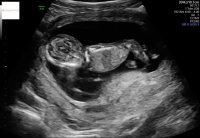

Så forliggende morkake. Om den ikke flytter seg kommer ikke babyen ut og det må det bli keisersnitt.. blir spennende å se

Ifølge jordmor lå morkaken min foran på magen. (Ul i uken12+1). Kan derfor kjenne spark noe senere enn andre som ikke har den på forsiden av magen. Føler jeg har kjent bevegelse allerede, minnet om slik det var med førstemann i uke 14, men usikker om det faktisk var babybevegelse pga. Morkakens plassering

Han sa ikke noe om hvor jeg har morkaken, men ser vel ut som at den ligger bak her?![]()